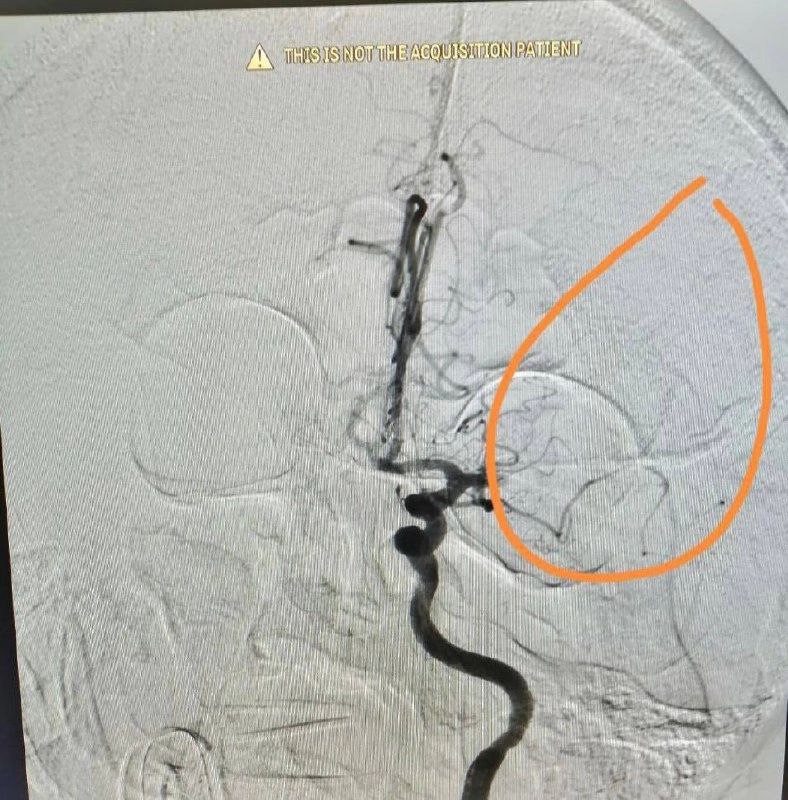

Пациент поступил в Орскую городскую больницу с ишемическим инсультом – на момент поступления у него полностью отнялась правая половина тела, также мужчина уже не мог говорить. Требовалось срочное вмешательство на внутримозговой артерии, а именно – механическое удаление тромба.

Прежде, чем провести операцию, хирурги убедились, что у поступившего пациента действительно закрыта крупная мозговая артерия, которую можно будет открыть. Выяснили это при помощи компьютерной томографии (ввели контрастное вещество, чтобы определить наличие тромба). Затем – срочно в операционную.

74-летнему мужчине успешно убрали тромб. Операция длилась около часа. Затем – реанимация, где за показателями пациента тщательно следили реаниматологи.

Уже спустя два дня у пациента не только «заработало» всё тело, но и восстановилась речь. Через 10 дней пациента отпустят домой.